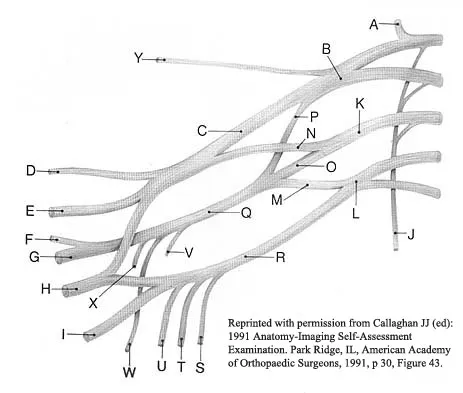

A patient who sustained a knife wound to the axilla 4 months ago now has profound interosseous wasting and generalized hand weakness. A brachial plexus injury is likely at which of the following locations in Figure 29?